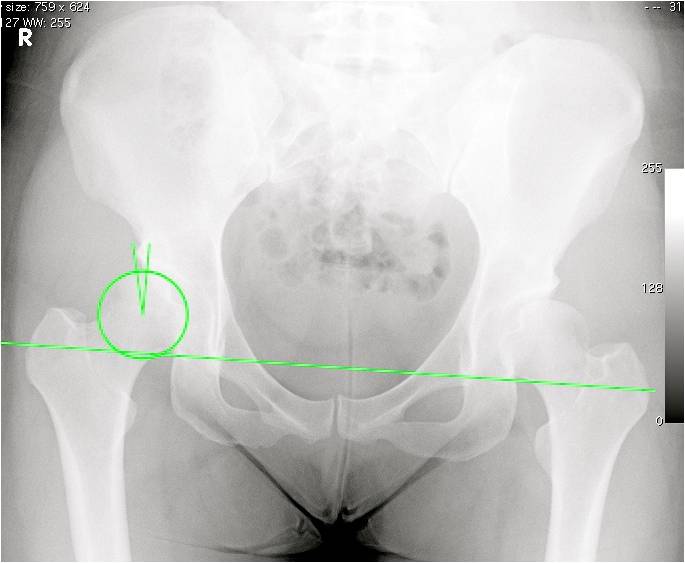

Congenital hip dysplasia. Xray of the hips of a woman with congenital Hip Dysplasia Knee Pain Mild hip dysplasia might not start causing symptoms until a person is a teenager or young adult. Recurring hip, groin or lateral hip pain; If you get pain on the outer side of your knee, in particular when standing or running, this can sometimes be caused by a hip problem. It is most often the term given to infantile hip.. Hip Dysplasia Knee Pain.

Complex THA for Severe Hip Dysplasia Darwin Chen, MD